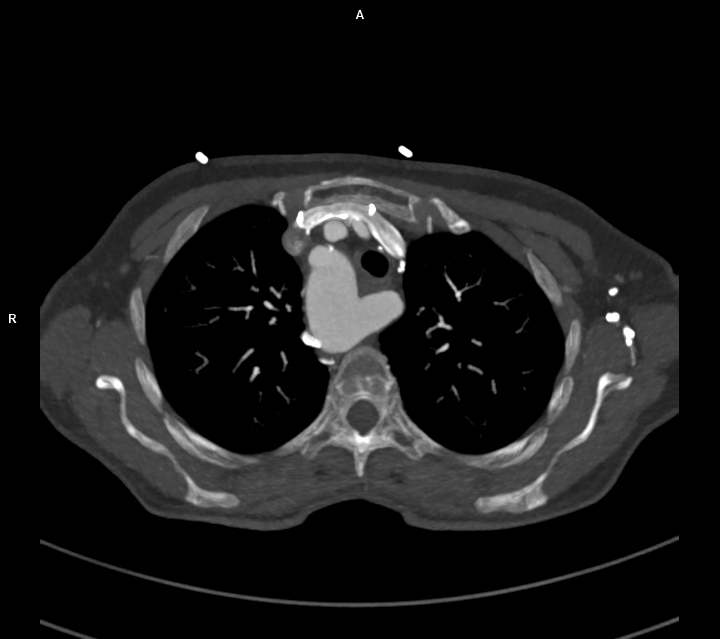

CAZ nr 57: Arc aortic de partea dreaptă si diverticul Kommerell

Figura 1: reconstrucție axială din achiziție angioCT toracică; se evidențiază arc aortic poziționat la dreapta cu originea arterei subclavii stângi dintr-o leziune cu aspect diverticular ce se dezvoltă posterior de trahee și esofag și anterior de coloana vertebrală tpracala – structura denumită diverticul Kommerell

Figura 3, 4, 5: reconstrucție de volum 3D din achiziție angioCT toracică

Discuţie caz nr 57:  pacient asimptomatic care a efectuat angioCT de aorta toracică pentru evaluarea unei creșteri de calibru a aortei la examinarea ecocardiografica. Este o anomalie de dezvoltare a arcului aortic, ce este situat la dreapta, cu originea arterei subclavii stângi dintr-o structura diverticulară.

DE LUAT ACASĂ!!! Diverticulul Kommerell este considerat a fi o eroare de dezvoltare a celui de-al patrulea arc aortic dorsal; a fost original descris la pacienții cu arc aortic la stânga ca o structura diverticulara de origine a arterei subclavii drepte aberante ce are origine din aorta după originea arterei subclavii stângi și apoi are traseu transmediastinal ajungând în fosa subclaviculară dreaptă (denumită și arteră lusoria pentru că produce la pacienți disfagie denumită disfagia lusoria).